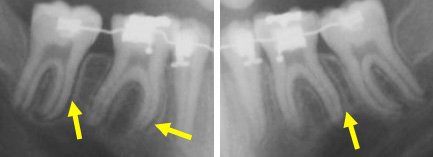

Avec l’utilisation d’une mécanique et des forces appropriées, il est possible de déplacer des dents sur des distances importantes (jusqu’à plus de 10 mm), comme dans ce cas où des molaires ont été avancées pour fermer un espace.

Lorsque les dents commencent à se déplacer, la zone du ligament parodontal (autour des dents) visible sur une radiographie et devient plus large (ligne foncée le long des racines). La ligne plus pâle est une couche d’os alvéolaire plus dense.